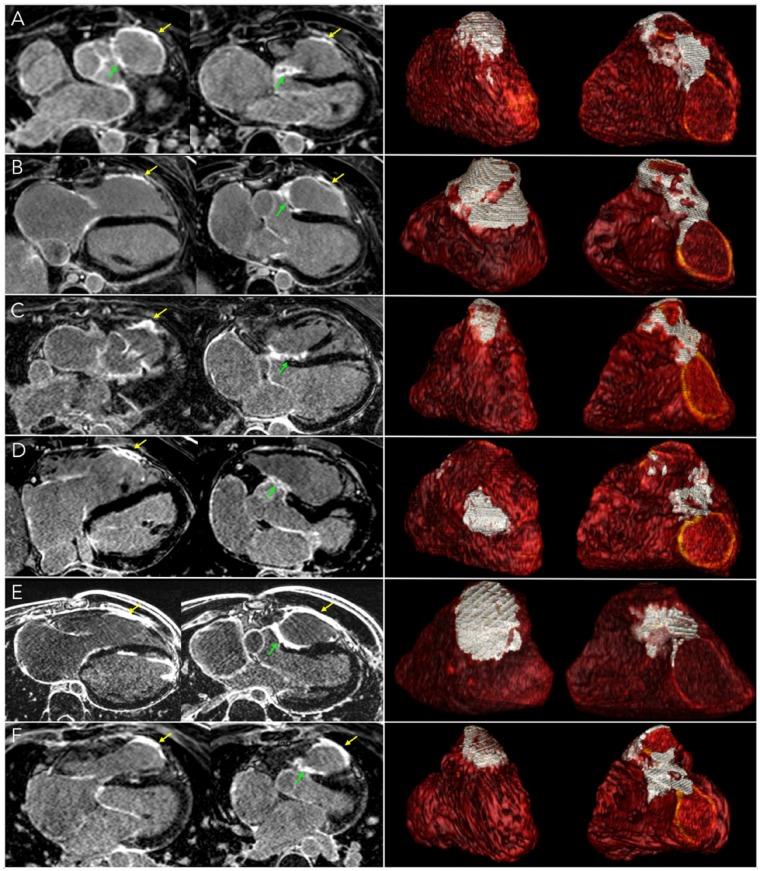

Consecutive patients with prior TOF repair underwent electrocardiogram, 24-h Holter, transthoracic echocardiography, exercise testing, and cardiac magnetic resonance (CMR) including cine imaging to assess ventricular volumes and ejection fraction, T1 mapping to assess left ventricular (LV) and right ventricular (RV) diffuse fibrosis, and free-breathing late gadolinium-enhanced imaging to quantify scar area at high spatial resolution. Structural imaging data were related to clinical characteristics and functional imaging markers. Cine and T1 mapping results were compared with 40 age- and sex-matched controls. One hundred and three patients were enrolled (age 28 ± 15 years, 36% women), including 36 with prior pulmonary valve replacement (PVR). Compared with controls, TOF showed lower LV ejection fraction (LVEF) and RV ejection fraction (RVEF), and higher RV volume, RV wall thickness, and native T1 and extracellular volume values on both ventricles. In TOF, scar area related to LVEF and RVEF, while LV and RV native T1 related to RV dilatation. On multivariable analysis, scar area and LV native T1 were independent correlates of ventricular arrhythmia, while RVEF was not. Patients with history of PVR showed larger scars on RV outflow tract but shorter LV and RV native T1.

CONCLUSION

连续的 TOF 修复后患者接受了心电图、24 小时 Holter、经胸超声心动图、运动试验和心脏磁共振(CMR)检查,包括电影成像以评估心室容积和射血分数、T1 映射以评估左心室(LV)和右心室(RV)弥漫性纤维化以及自由呼吸式晚期钆增强成像以高空间分辨率量化瘢痕面积。结构成像数据与临床特征和功能成像标志物相关。比较电影和 T1 映射结果与 40 名年龄和性别匹配的对照。共纳入 103 名患者(年龄 28±15 岁,36%为女性),其中 36 名患者有既往肺动脉瓣置换术(PVR)。与对照组相比,TOF 的 LV 射血分数(LVEF)和 RV 射血分数(RVEF)较低,RV 容积、RV 壁厚度以及心室的原始 T1 和细胞外容积值较高。在 TOF 中,瘢痕面积与 LVEF 和 RVEF 相关,而 LV 和 RV 原始 T1 与 RV 扩张相关。多变量分析表明,瘢痕面积和 LV 原始 T1 是室性心律失常的独立相关因素,而 RVEF 不是。有 PVR 病史的患者 RV 流出道有较大的瘢痕,但 LV 和 RV 原始 T1 较短。

结论